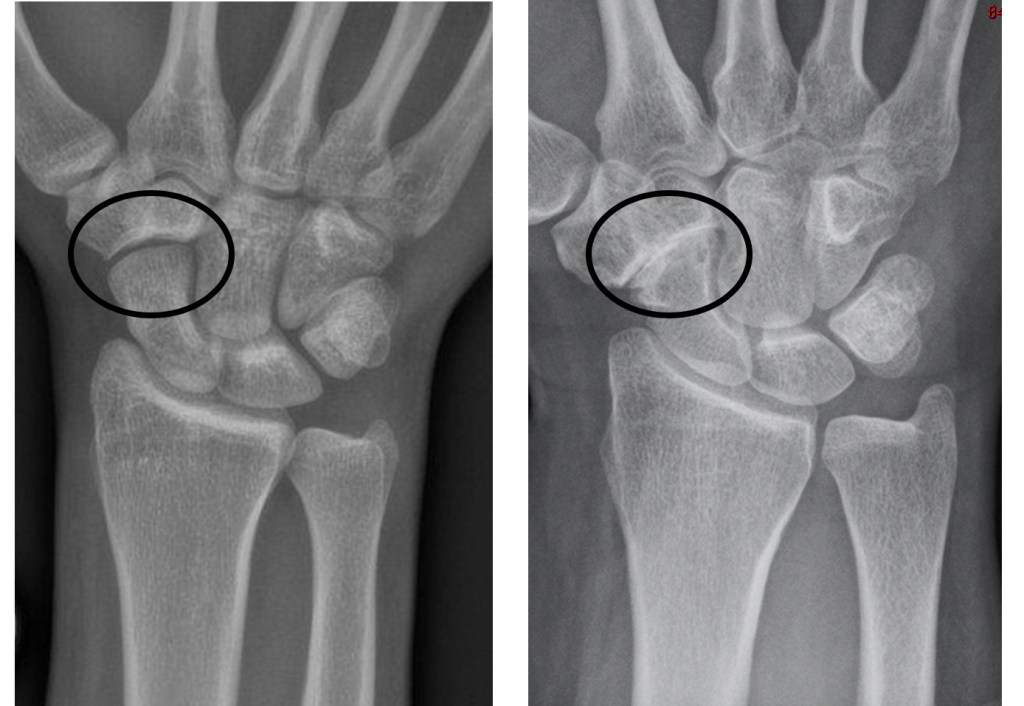

The diagnosis of triscaphoid arthritis is made from the symptoms and signs, and is confirmed on an xray of the wrist. The gap seen on X-rays between bones is not a real gap – it is filled with smooth cartilage (the lining of the joint) in order to allow smooth movement. In arthritis, the cartilage is lost, and therefore the gap between the bones appears diminished.